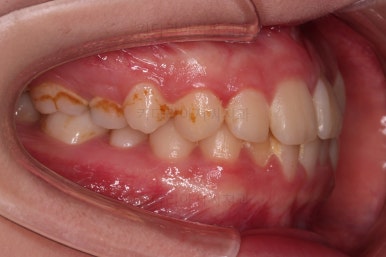

장치를 처음 부착한 사진입니다.

이번 환자분은 특징적으로 윗니의 장치와 아랫니의 장치가 다르죠.

윗니는 좀 더 심미적인 세라믹으로 선택하셨고 아랫니는 비교적 저렴하고 부피가 약간 작고 튼튼한 메탈로 진행했습니다.